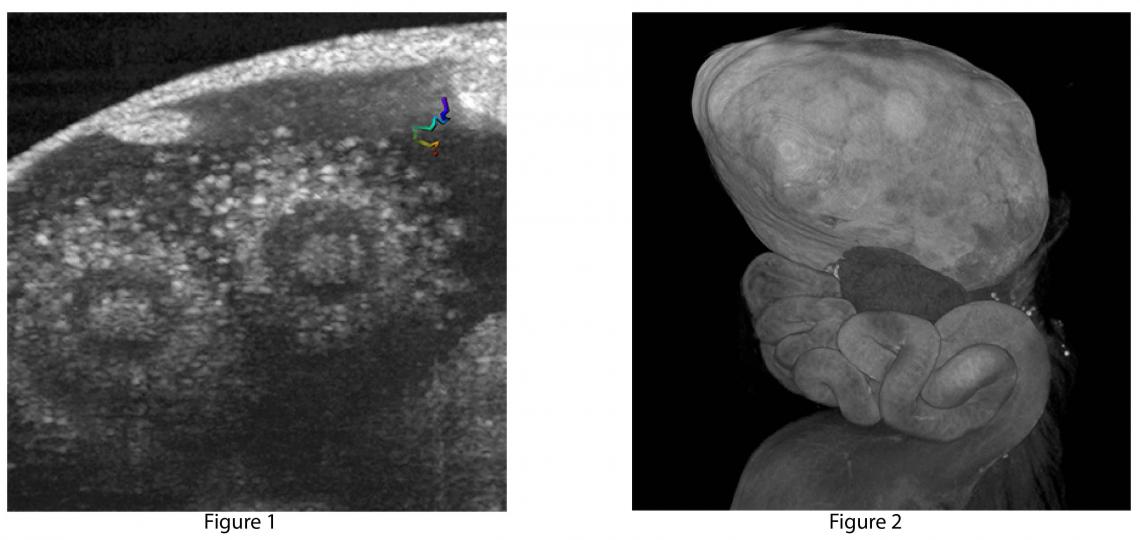

Images from Larina Laboratory

Figure 1: Individual sperm tracking (colored line) toward ovulated eggs within in the mouse oviduct captured in vivo with optical coherence tomography. Image from Shang Wang, PhD, a postdoctoral fellow in the Larina Laboratory.

Figure 2: The mouse female reproduction system imaged with microcomputed tomography (micro-CT) Image by Zheng-Chen Yao in the Larina Lab